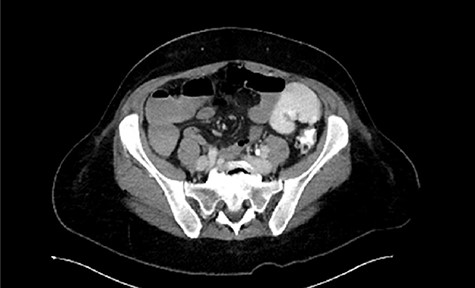

Immediate postoperative course was uneventful until postoperative day (POD)-5 when she experienced multiple watery stools, diffuse abdominal pain, fever (102.6F) and leukocytosis (23000/UL). Clostridium difficile infection was ruled out with a negative stool toxin assay. Her abdominal exam remained nonspecific until POD-6 when she had bilious emesis. A computed tomography (CT) scan revealed perforated diverticulitis with pelvic abscess and multiple colonic diverticulitis with an associated small bowel obstruction (SBO) (Images 1–4). No prior history of diverticulitis was reported.

She was managed with bowel rest, intravenous fluids, nasogastric tube suction and analgesics and empirically started on broad-spectrum gram negative and anaerobic antibiotics. Her pelvic abscess was drained percutaneously with one trans-gluteal drain. She improved significantly with some return of GI function on POD-7. Because of persistent leukocytosis, a follow-up CT scan was done 5 days post-drain placement which showed marked improvement of the pelvic abscess (Image 5). She was discharged home on ceftriaxone and oral metronidazole on POD-16 to complete a total of 14 days antibiotic treatment. The drain was removed before discharge. She reported no abdominal symptoms during her 1-month follow-up.

Follow-up CT showing marked improvement of pelvic abscess collection.